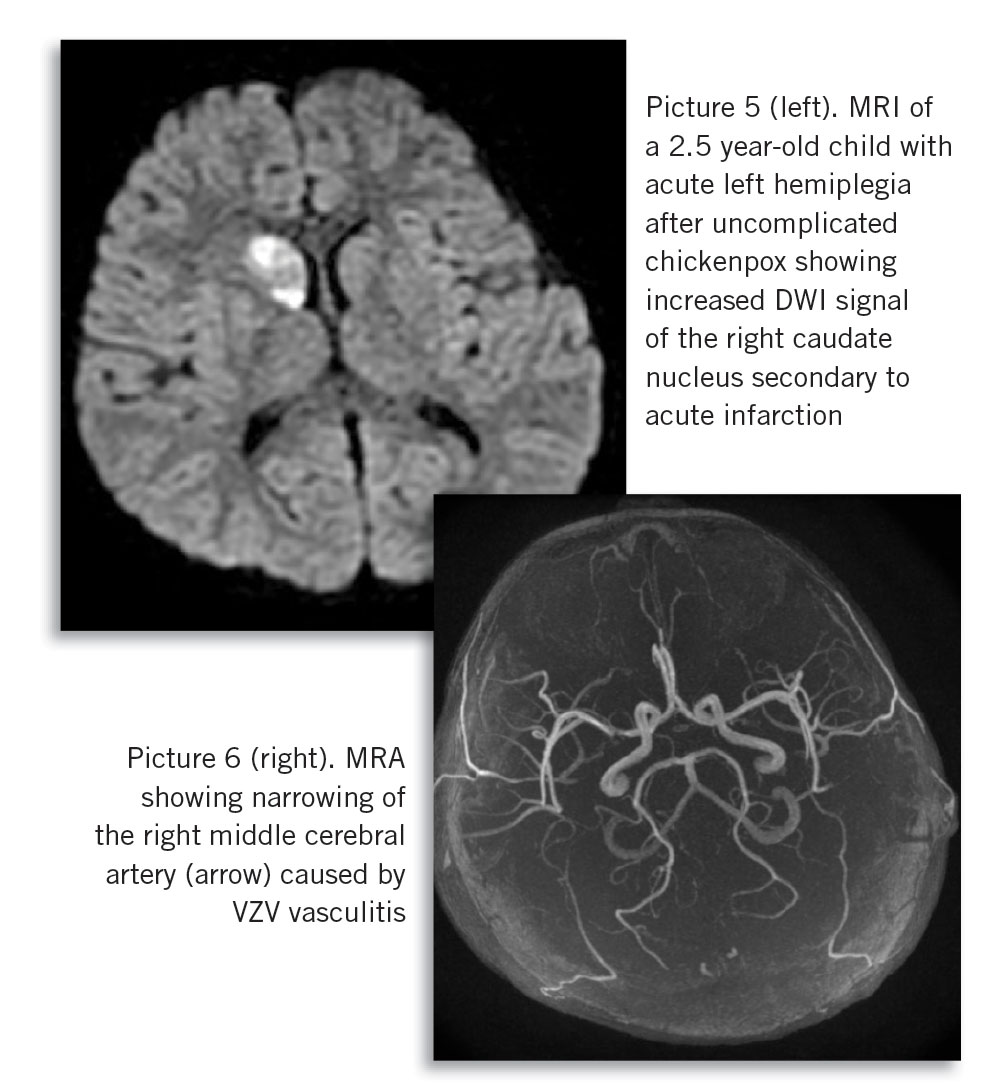

Secondary iGAS or staphylococcal disease is potentially life or limb-threatening. Chickenpox is the most common risk factor for paediatric iGAS disease, including necrotising fasciitis and toxic shock-like syndrome (see Picture 3). Hospitalisations due to iGAS disease have been increasing in Ireland over the past decade.2 In a recent series of iGAS cases presenting to the Temple Street Hospital, 70% had active chickenpox.

Bacterial super-infection (see Picture 4) complicating chickenpox should be suspected in any child with fever that persists or recurs beyond four to five days of illness, where severity of pain is disproportionate, or with redness and swelling around skin lesions.